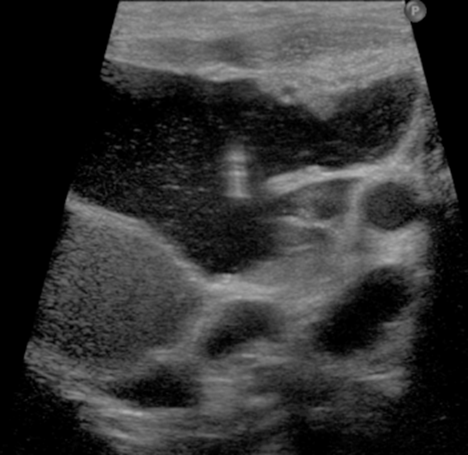

The lesions are most commonly evaluated with contrast enhanced MRI. Occasionally US and CT are used.

A team approach is utilized in the treatment of vascular malformations. The Division of Internvational Neuroradiology (DINR) is part of a combined center, The Vascular Birthmark Clinic. The following specialties may be involved depending on the location of the lesion: dermatology, otolaygology, plastic surgery, ophthalmology, oromaxillofacial surgery, and neuro-interventional radiology. Often, minimally invasive image guided percutaneous sclerotherapy is successful for the low flow venous and veno-lymphatic malformations. In this procedure X-ray and\or high resolution ultrasound guidance is used to inject a sclerosant into the malformation to damage the cells lining the lesion so that the fluid in the lesion does not re-accumulate. Sometimes several sclerotherapy sessions may be necessary. Patients typically go home on the day of the procedure.